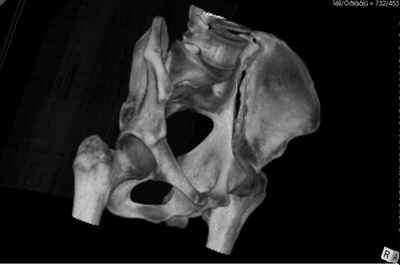

Уважаемые коллеги! В даном конкретном случае речь идет о "ложном суставе", поэтому показано реконструктивно-восстанвоительная операция т.е. остеотомия по линии "ложного сустава" затем остеосинтез реконструктивными пластинами, мы выбрали пахово-подвздошный (с наружным) доступ т.к. линия излома проходит на крышу вертлужной впадины. С уважением Ерсин Жунусов

Андрей, на 3d снимках не видно соотношение суставных поверхностей, величину диастаза в ложном суставе и состояние головки (может уже протез нужен).

Нужны стандартные снимки и срезы на уровне сустава и тела подвздошной кости.